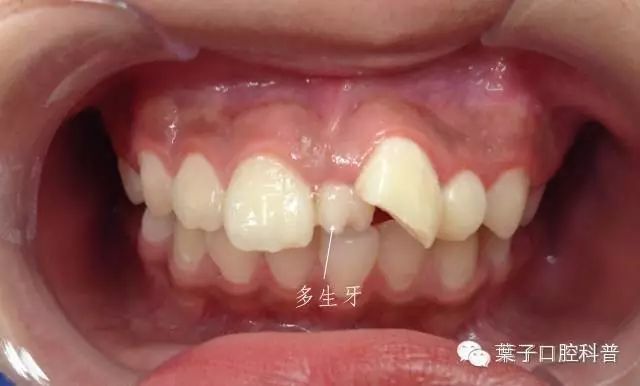

还有一位小朋友,在上门牙里面又长出来两个尖尖的牙齿。这也是多生牙。

这个小朋友的多生牙占据了门牙的位置,但由于多生牙没有及时拔除,影响了其它正常牙齿的排列。这时,门牙只能占据侧切牙的位置,那侧切牙只能委屈地排列在门牙的后面,那里不拥挤而且凉快哦。

这位小朋友也一样,由于两颗门牙之间有多生牙先行萌出,导致左上门牙不能萌出到正常位置,只能向外侧萌出,俗称“牙齿龅出来”了。如果受到外伤,这颗牙会很容易折断。